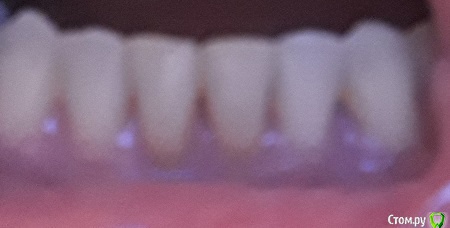

nata* Опубликовано 4 августа, 2019 Автор Поделиться Опубликовано 4 августа, 2019 Спасибо за ответ! Вот фото Ссылка на комментарий

nata* Опубликовано 4 августа, 2019 Автор Поделиться Опубликовано 4 августа, 2019 Когда снимаю камень зубной, еще больше становятся щели Ссылка на комментарий

nata* Опубликовано 8 августа, 2019 Автор Поделиться Опубликовано 8 августа, 2019 Это я все делаю, но можно ли черные треугольники как-то закрыть?? Ссылка на комментарий

Doc Опубликовано 9 августа, 2019 Поделиться Опубликовано 9 августа, 2019 Иногда пародонтологи своими лоскутными операциями такие треугольники закрывают. Но не всегда это удается сделать. Другой вариант - виниры. А больше вариантов нет. 1 Ссылка на комментарий